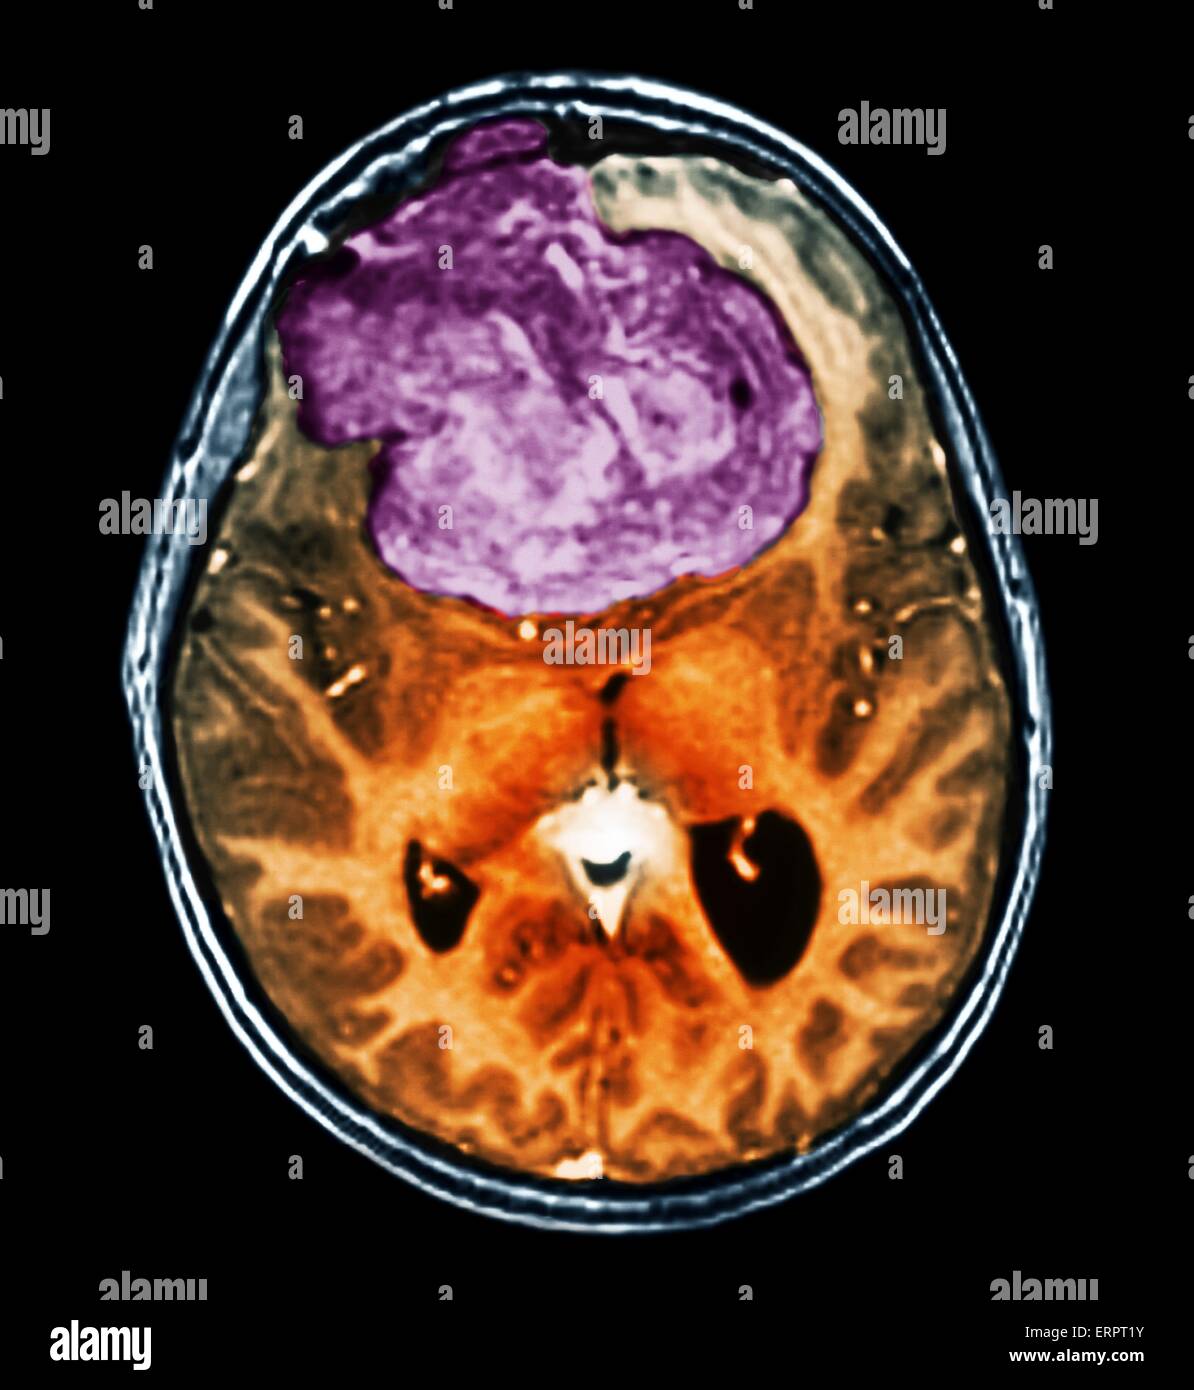

Tumeur bénigne au cerveau. La tomodensitométrie (CT de couleur) du cerveau d'un patient de 25 ans avec un méningiome (violet). Il s'agit d'une bénigne (non cancéreuse) tumeur qui découle de la méninges, les membranes qui entourent le cerveau. Il a été causé par ra Banque D'Imageshttps://www.alamyimages.fr/image-license-details/?v=1https://www.alamyimages.fr/photo-image-tumeur-benigne-au-cerveau-la-tomodensitometrie-ct-de-couleur-du-cerveau-d-un-patient-de-25-ans-avec-un-meningiome-violet-il-s-agit-d-une-benigne-non-cancereuse-tumeur-qui-decoule-de-la-meninges-les-membranes-qui-entourent-le-cerveau-il-a-ete-cause-par-ra-83480375.html

Tumeur bénigne au cerveau. La tomodensitométrie (CT de couleur) du cerveau d'un patient de 25 ans avec un méningiome (violet). Il s'agit d'une bénigne (non cancéreuse) tumeur qui découle de la méninges, les membranes qui entourent le cerveau. Il a été causé par ra Banque D'Imageshttps://www.alamyimages.fr/image-license-details/?v=1https://www.alamyimages.fr/photo-image-tumeur-benigne-au-cerveau-la-tomodensitometrie-ct-de-couleur-du-cerveau-d-un-patient-de-25-ans-avec-un-meningiome-violet-il-s-agit-d-une-benigne-non-cancereuse-tumeur-qui-decoule-de-la-meninges-les-membranes-qui-entourent-le-cerveau-il-a-ete-cause-par-ra-83480375.htmlRFERPT1Y–Tumeur bénigne au cerveau. La tomodensitométrie (CT de couleur) du cerveau d'un patient de 25 ans avec un méningiome (violet). Il s'agit d'une bénigne (non cancéreuse) tumeur qui découle de la méninges, les membranes qui entourent le cerveau. Il a été causé par ra